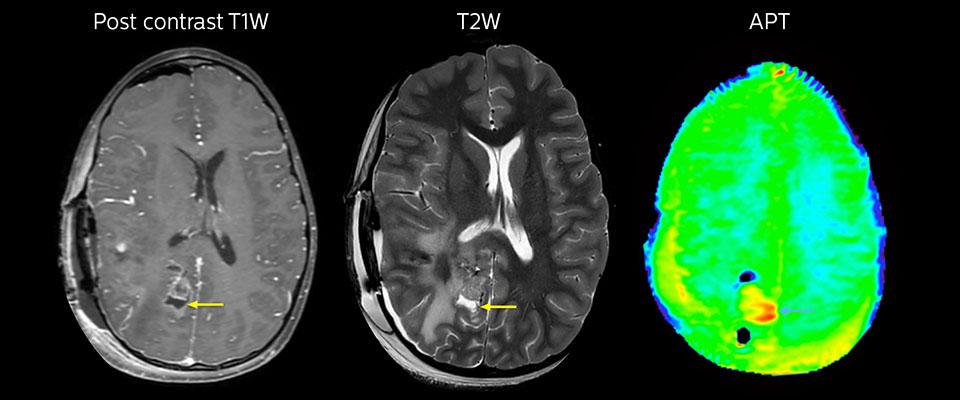

Large metastatic brain lesion

This 10-year-old patient underwent Ewing’s sarcoma tumor resection 7 years ago, but was found to now have a large metastatic lesion in the brain. This lesion shows clearly increased APT signal.

MRI with APT post resection

Immediately post resection MRI was again performed. T2-weighted and postcontrast T1-weighted images are quite inconclusive for distinguishing residual tumor tissue from postoperative tissue changes. On the APT image some high signal is still seen, which would suggest residual tumor tissue.

Follow-up over time

In later follow-up scans the post-contrast T1-weighted images suggest recurrent tumor growth. So, it would be interesting to study the predictive value of APT in a large patient group.